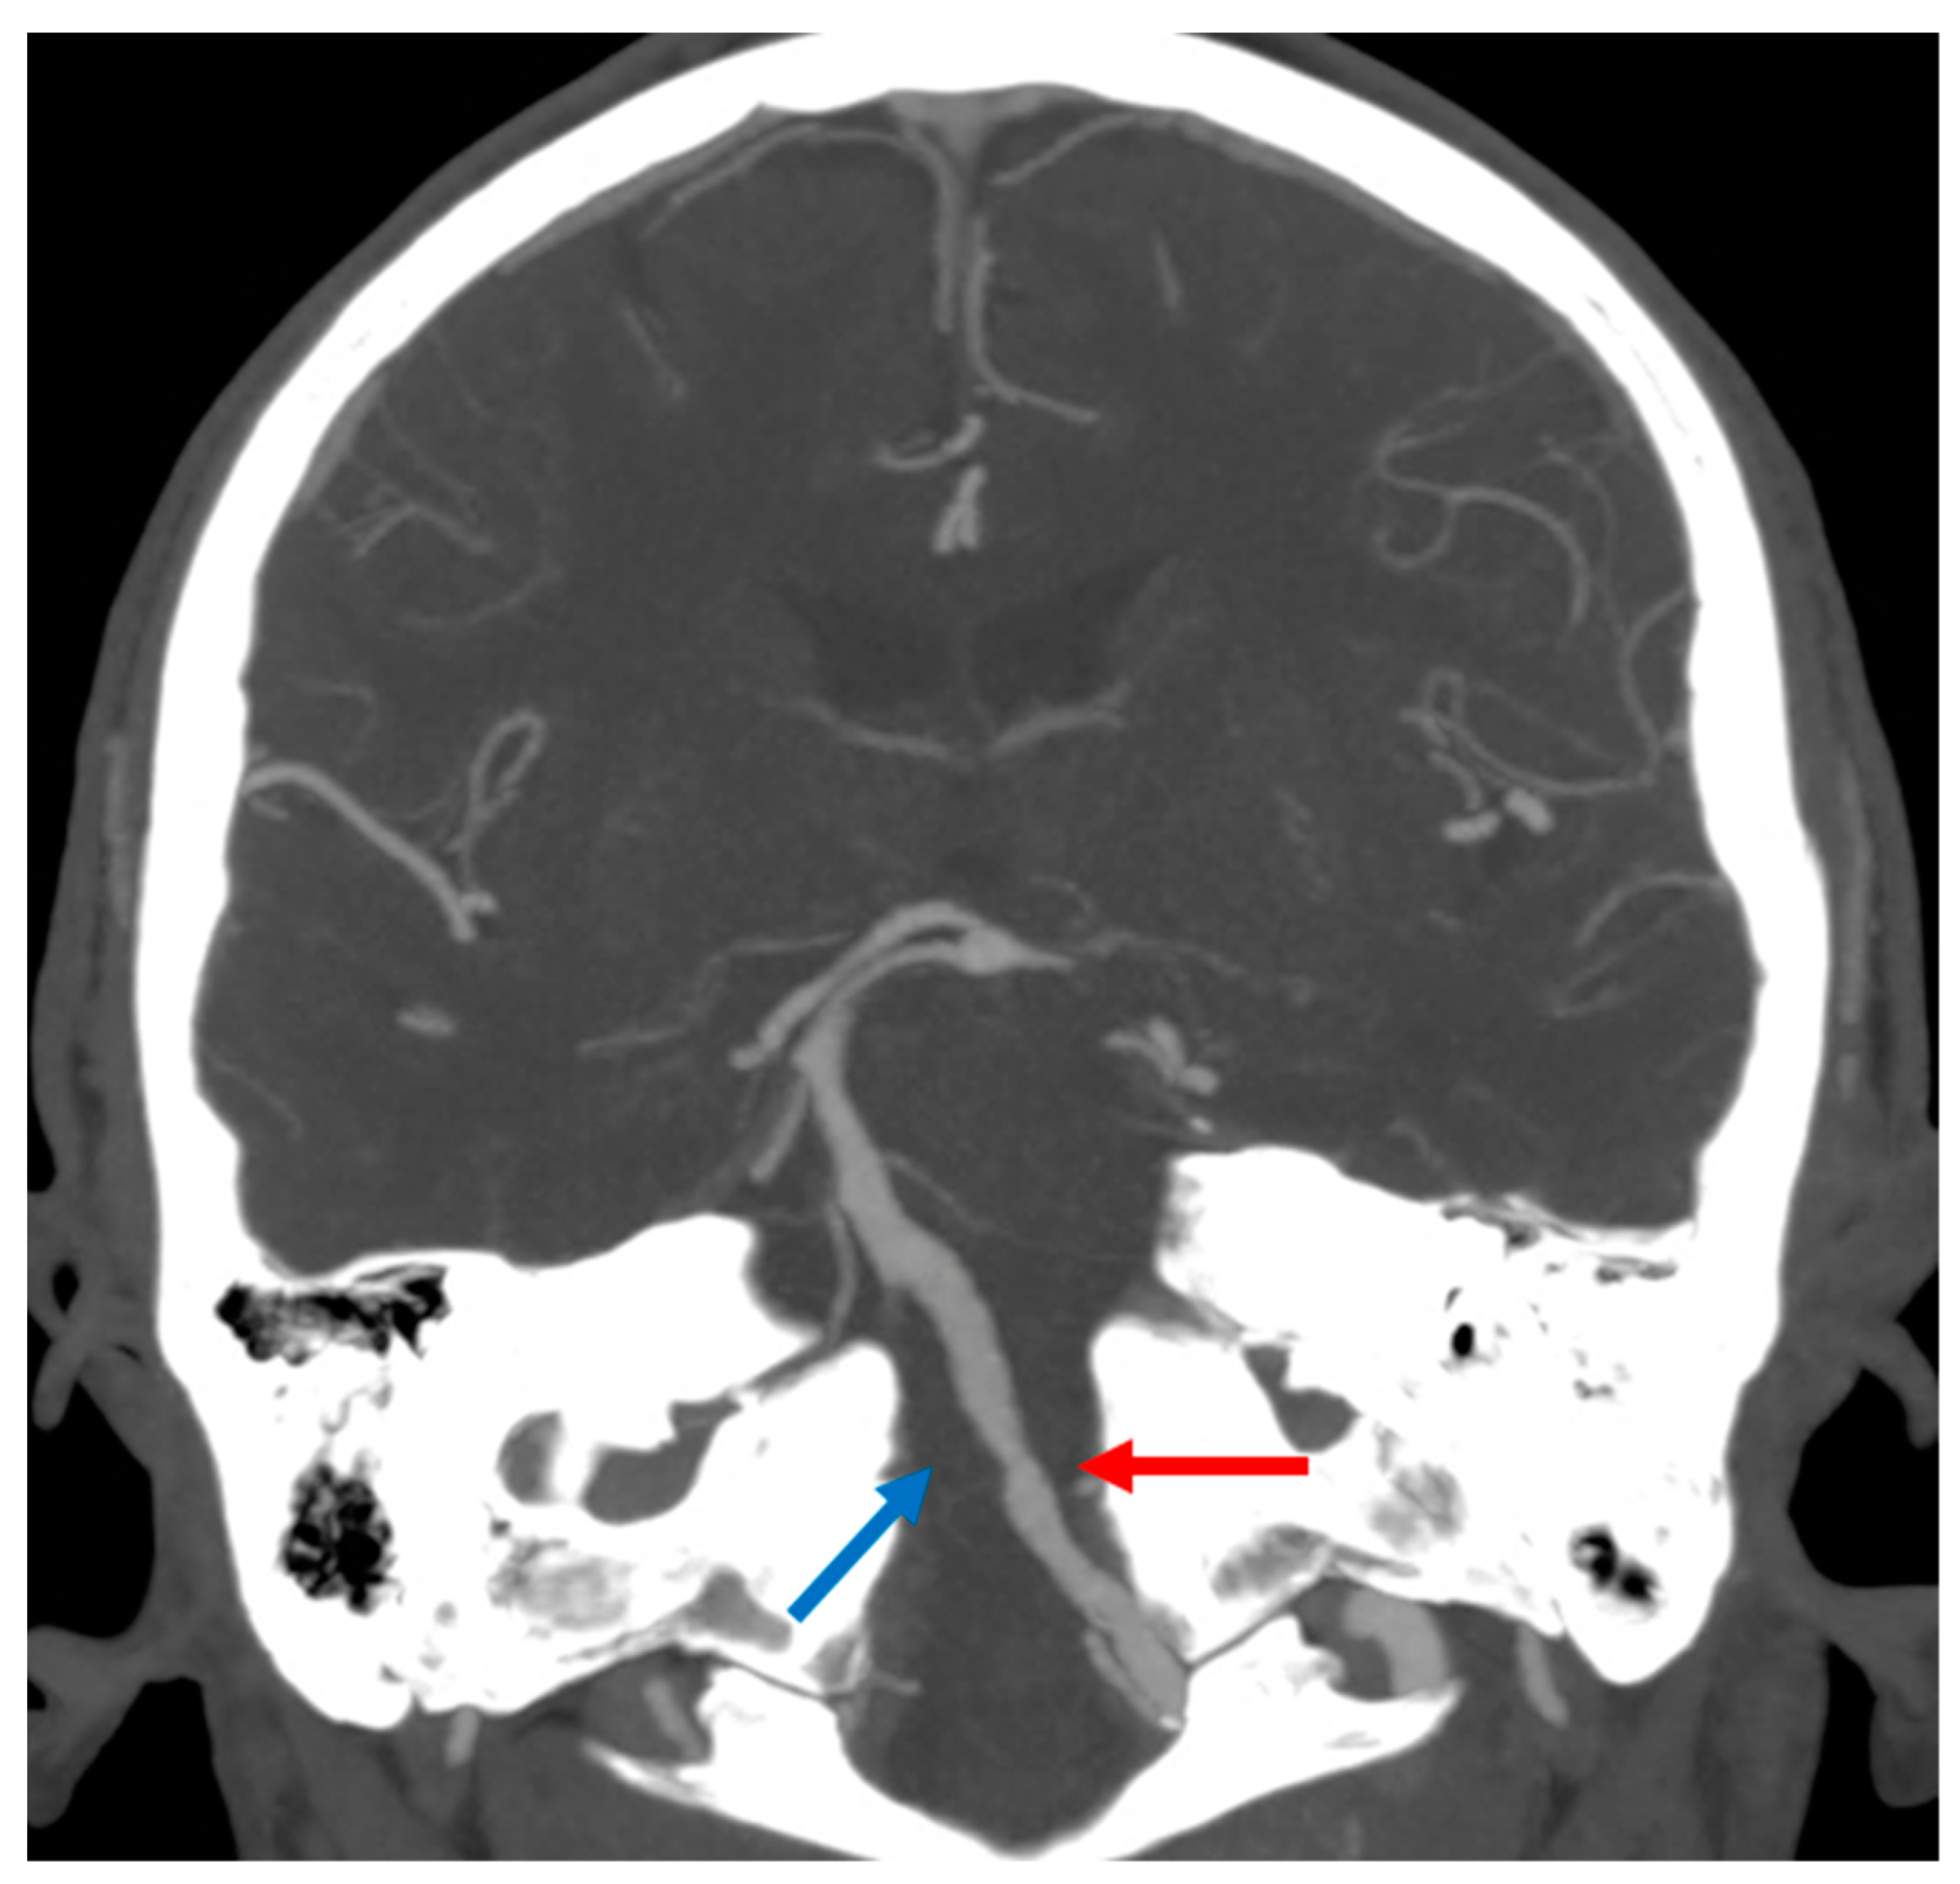

3.1. Medullary Infarction

3.2. Pontine Infarction

3.3. Midbrain Infarction